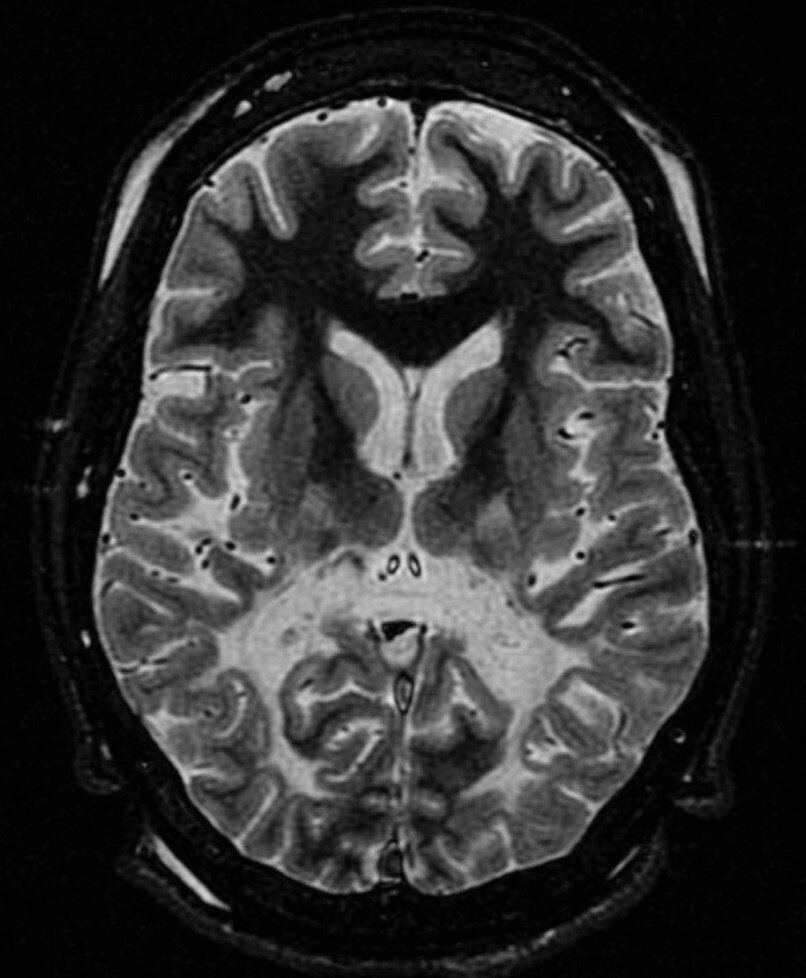

Teshamae Monteith is the Head of the Headache Unit at the University of Miami Health System, advocating for a better understanding of migraines as a serious health issue rather than a mere psychological ailment.

Hürriyet: Sadece baş ağrısı mı, yoksa beyinde bir alarm mı? Migrene dair bildiklerimiz değişiyor